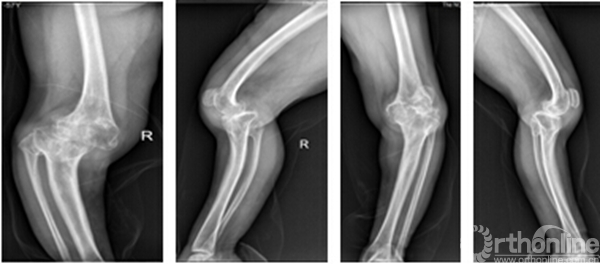

李某某,女,60岁,双侧膝关节疼痛、活动受限并伴股骨胫骨畸形40余年,其股骨远端前弓大,股骨前髁小,后髁大,胫骨近端后外弓30°,股骨髁及胫骨平台发育小,KSS评分15分,患者来我院就诊,要求行手术治疗改善外观及生活质量。

术前X光片正侧位 右侧 左侧